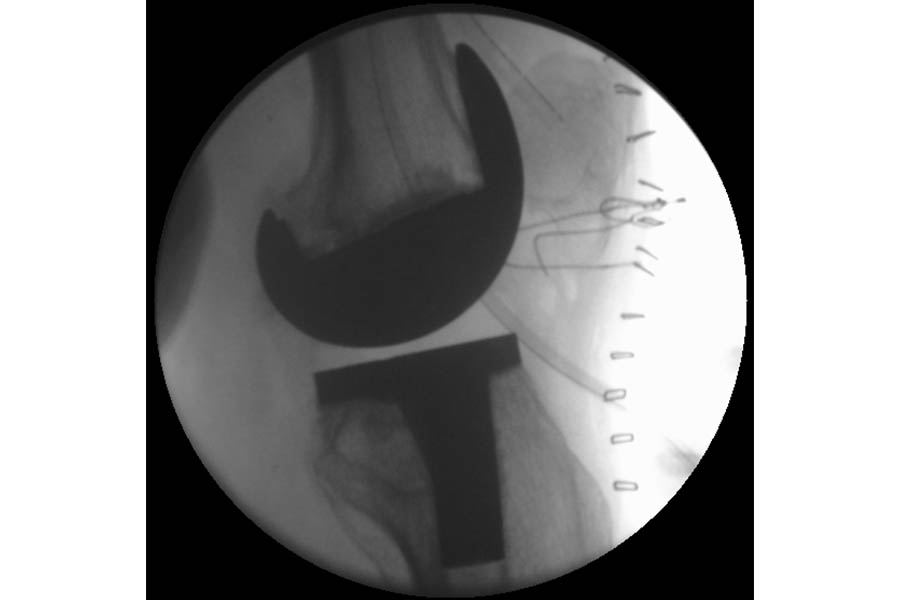

Difficult Replacement

Case 1